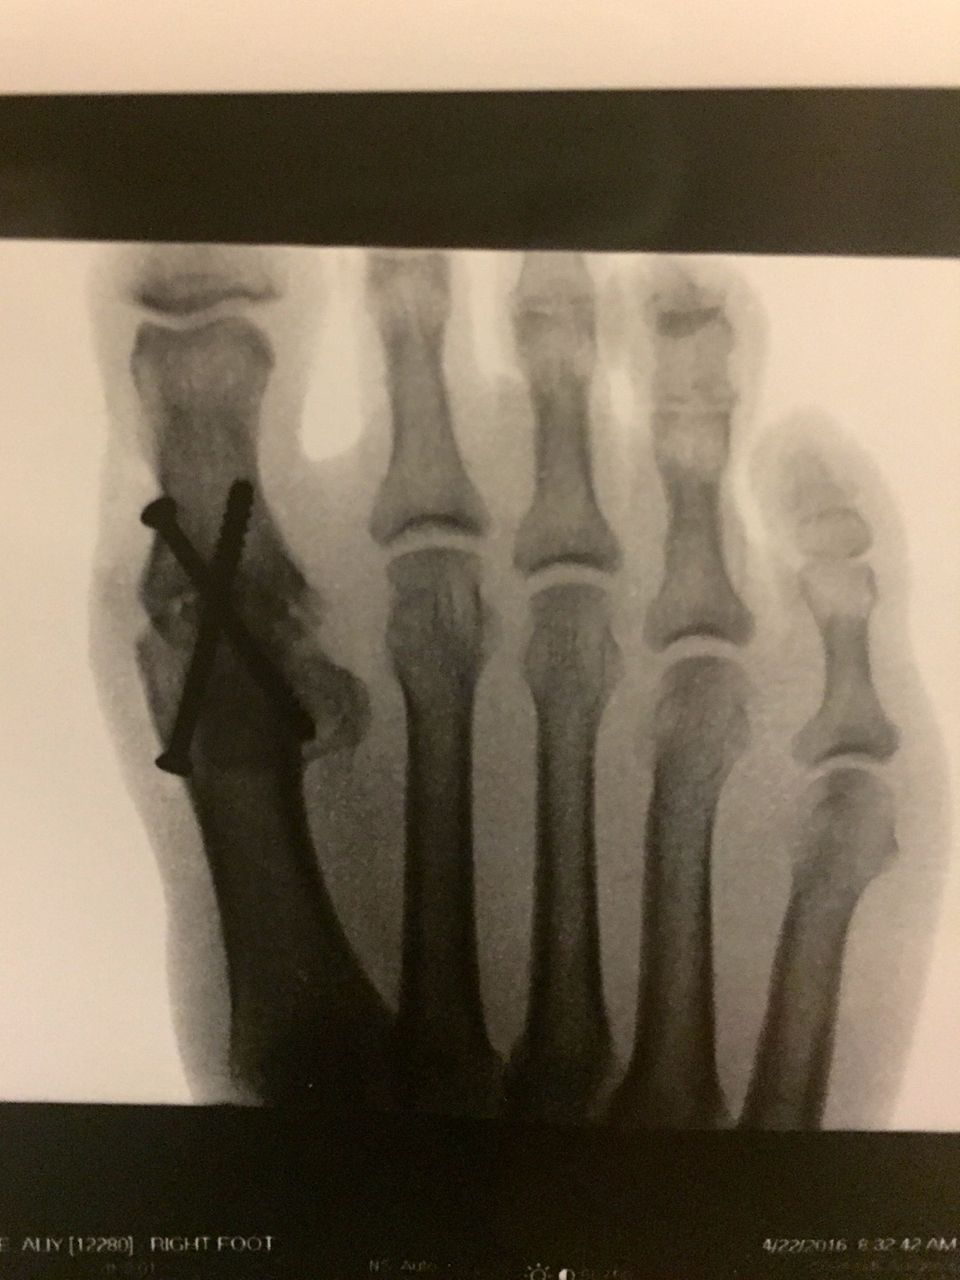

The surgery went well — according to Ken — who drew husky faces on my now bionic right foot and showed us the X-rays on which you can see the hardware. The surgery basically removed the big toe joint (which was a mess) and then screwed the two bones together. Now they must fuse – like a broken bone would do. So, that means it will be 4 to 6 weeks of non weight bearing on my right foot.

Thank you for including the picture of the xray. I couldn't have imagined that X.